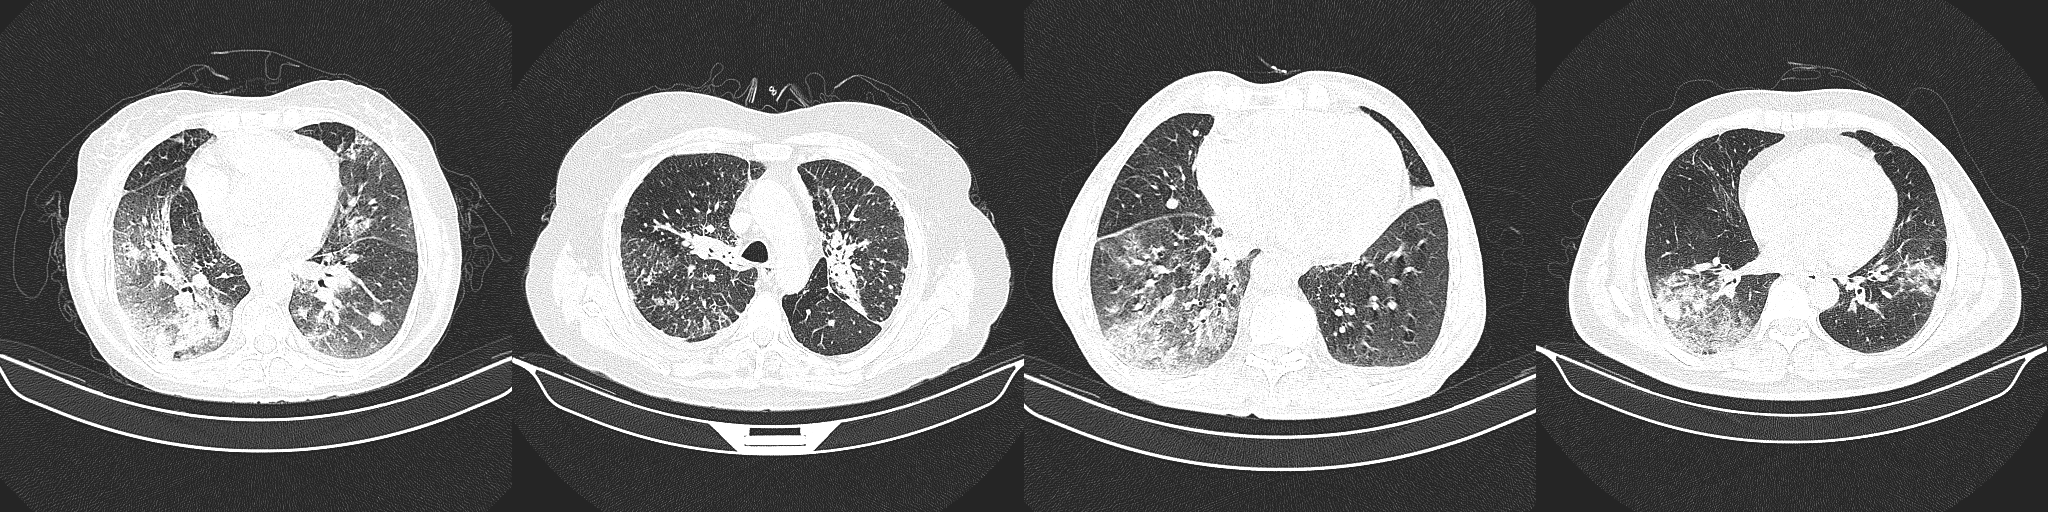

The proposed COVIDNet-CT was pre-trained on the ImageNet [36] dataset and then trained on the COVIDx-CT dataset via stochastic gradient descent with momentum [37]. The hyperparameters used for training are as follows: learning rate=5e-3, momentum=0.9, number of epochs=17, batch size=8. Data augmentation was applied with the following augmentation types: cropping box jitter, rotation, horizontal and vertical shear, horizontal flip, and intensity shift and scaling. In initial experiments, it was found via explainability-driven performance validation (see Section 3.5 for more details on the methodology) that erroneous indicators in the CT images (e.g., patient tables of the CT scanners, imaging artifacts, etc.) were being leveraged by the network to make predictions. To help prevent this behaviour, we introduce an additional augmentation which removes any visual indicators which lie outside of the patient’s body, as illustrated in Figure 5. Finally, we adopt a batch re-balancing strategy similar to that employed in [18] to ensure a balanced distribution of each infection type at the batch level. The proposed COVIDNet-CT was implemented, trained, and evaluated using the TensorFlow deep learning library [38].

Figure 5: Example COVID-19 case before and after removal of irrelevant visual indicators as part of data augmentation. In (a), a number of irrelevant visual indicators are present, such as the patient table of the CT scanner as well as imaging artifacts. After removing these irrelevant indicators, the image in (b) is obtained.